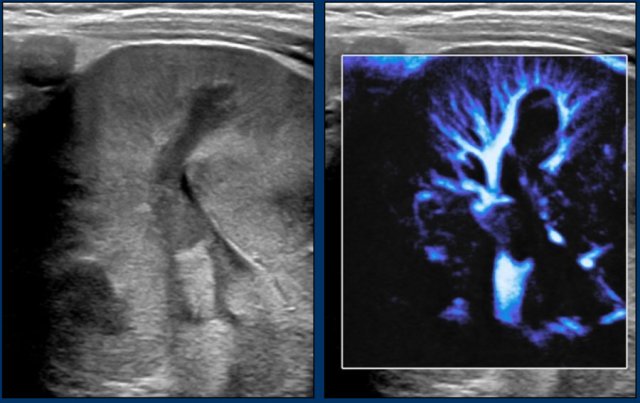

Renal cell carcinoma

Renal cell carcinoma (RCC) is the second most common renal tumor in children.

RCC is rare in young children and occurs mostly in children older than 10 years.

It can also occur in patients with von Hippel-Lindau disease and Tuberous Sclerosis Complex, or after treatment for previous malignancies (f.e Neuroblastoma or Leukemia)

Image

A nine-year-old boy presented with severe hematuria.

On palpation a left abdominal mass was found.

On ultrasound a predominantly solid mass was seen which seemed to invade the dilated collecting system.

On imaging renal cell carcinomas can present in many different ways.

They can appear more solid or have cystic elements and may be homogeneous, or rather heterogeneous.

Hemorrhage can occur and they may contain fat.

Relative small tumor size and prominent peripheral vessels suggests a RCC.

Imaging is essential for staging and a combination of ultrasound, CT and MRI is used.

video

MRI nicely demonstrates the mass in the left kidney. Note the large collateral veins.

Because of heavy hematuria a left nephrectomy was performed.

Pathology showed a RCC which was completely resected.